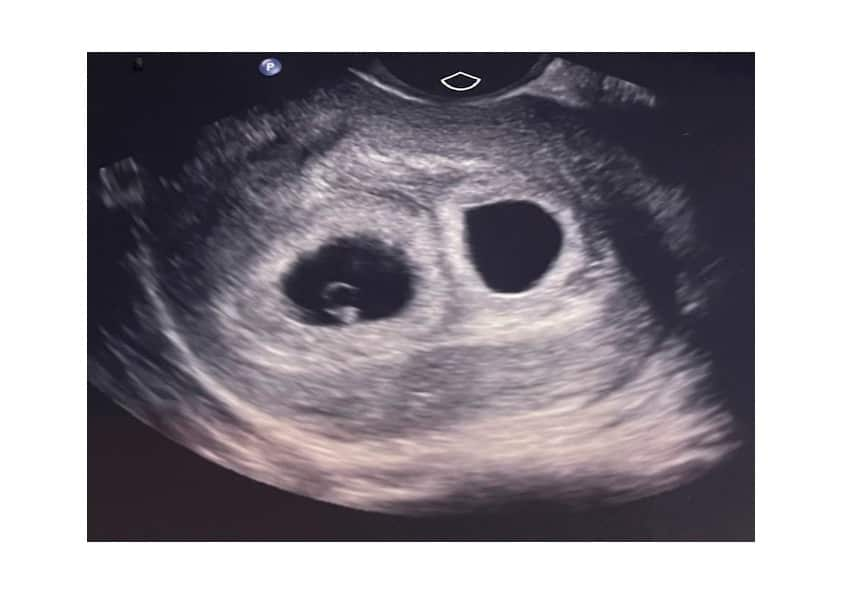

After 17 rounds of IVF over about three years, Vali and Dean's six-week scan revealed incredible images: two developing embryos.

"We were all crying, and they called Kate (Stern) and she was crying," Vali said.

"And that was just the first little black hole that they saw on the screen. Then [the sonographer] moved the probe and there was another one. So I think I was just in shock.